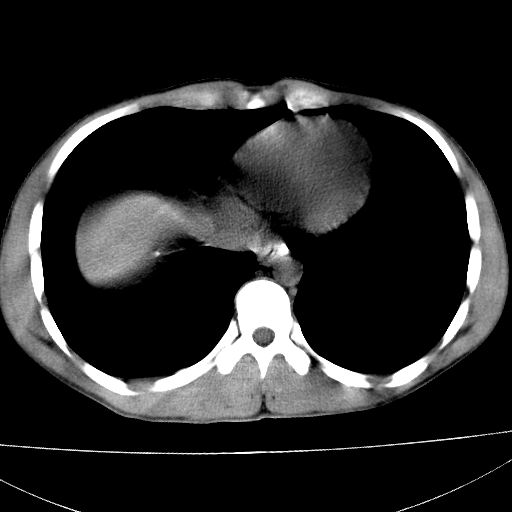

标题: CT15860:男,21岁,腹部外伤2小时伴胸疼。 [打印本页]

标题: CT15860:男,21岁,腹部外伤2小时伴胸疼。

b超示:肝破裂。

肝脏及肾脏明显有损伤性改变并激发腹腔内积液(血),以肝脏撕裂及肾周积血显著。

1)肝破裂伴腹腔积液(血)。2)右肾破裂伴右肾包膜下及肾周血肿。3)腹部空腔脏器穿孔可能。4)右侧少量胸腔积液(血)。